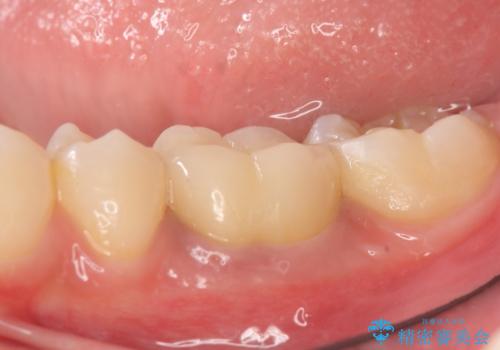

折れた前歯のセラミック修復 根管治療のやり直しもおこなう

前歯が折れてしまい、審美的に大きな問題となっていたため、まずは仮歯にて見た目の回復をしました。

根管治療に関しては、悩んだ結果やり直しを選択され、やや時間はかかってしまいましたが、基礎からしっかりとやり直すことができました。

被せものの種類:PFZ standard